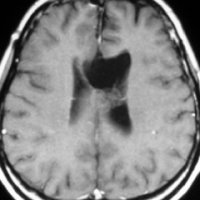

放射線誘発膠芽腫(グリオブラストーマ)

松果体のジャーミノーマのために,19歳の時に全脳照射30グレイと松果体局所照射20グレイを受けました。これは28歳の時に発生した右側頭葉の膠芽腫です。この部分には30グレイしか入っていないのですが,2.5グレイという大きな1日線量が用いられていました。またslit-beam rotationという1990年代初頭に用いられた照射方がされています。同じ線量であっても二次ガンを招きやすい照射法というのがあるのかもしれません。